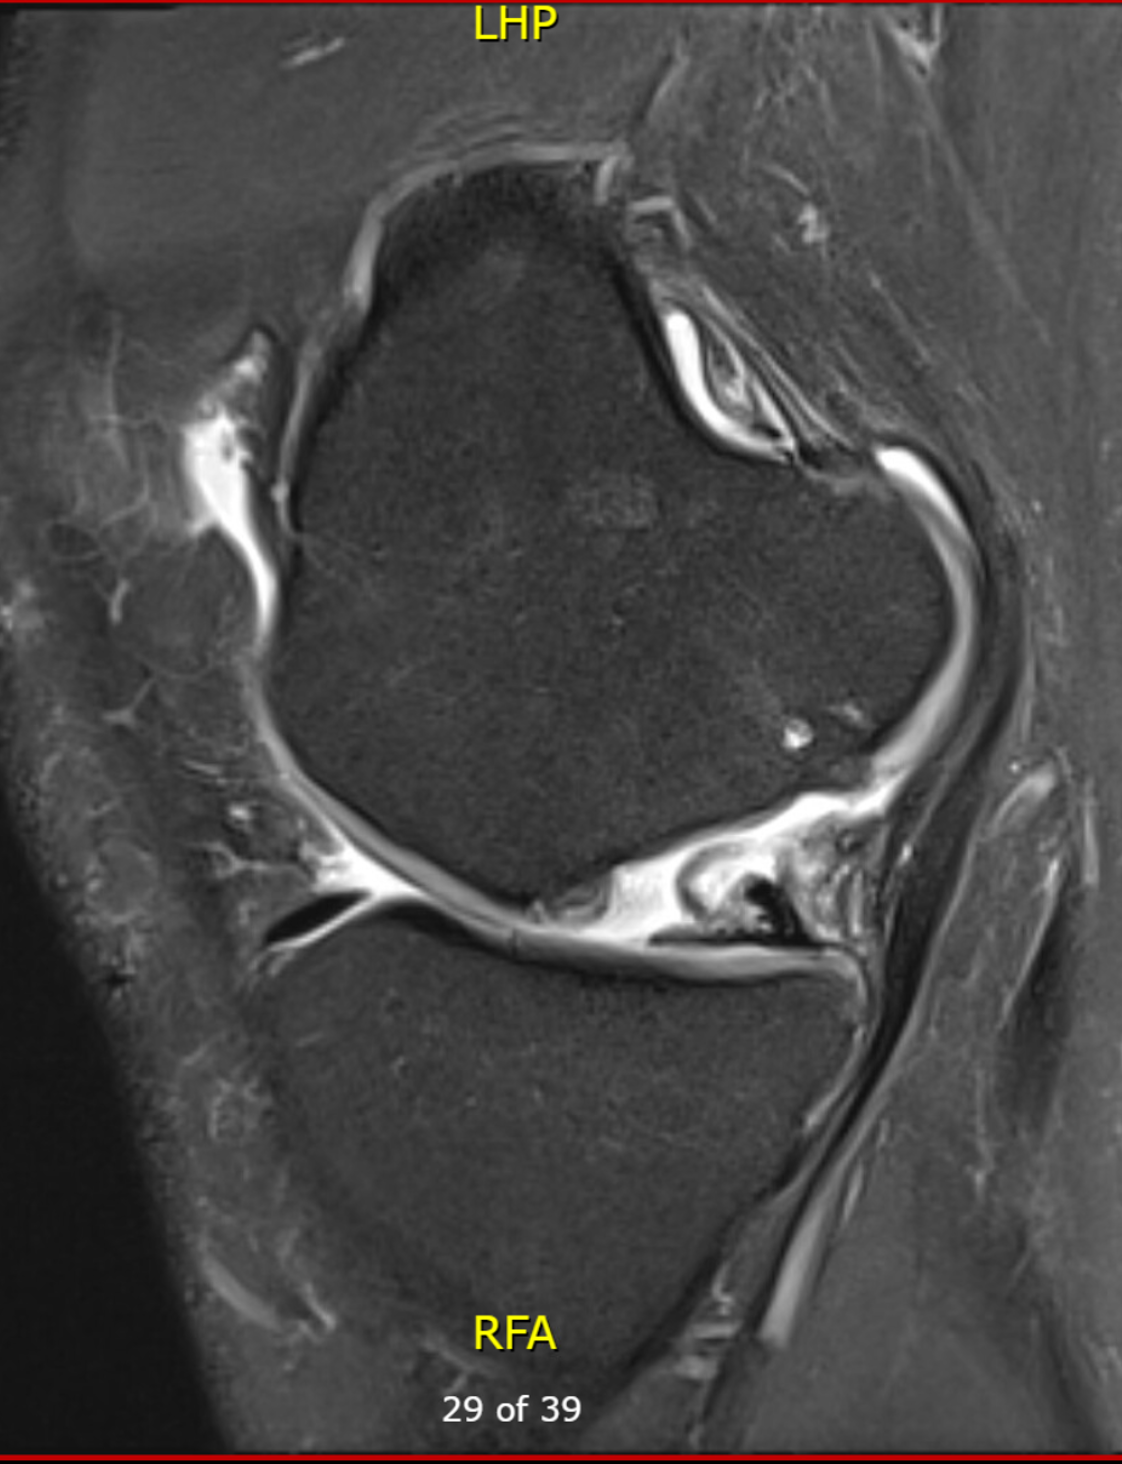

Osteochondral defect